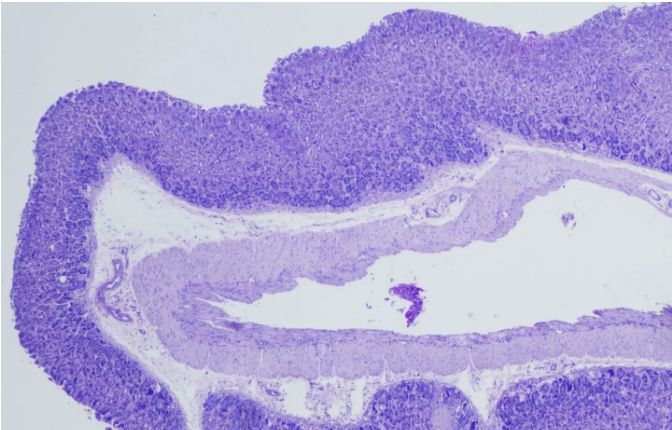

PAS染色實(shí)驗(yàn)過程中常見問題解答由普拉特澤生物為大家總結(jié)分享。PAS染色作為一種在組織學(xué)中廣泛應(yīng)用的染色技術(shù),雖然具有高度的特異性和敏感性,但在實(shí)際操作過程中,也常會(huì)遇到一些問題和挑戰(zhàn)。本文是關(guān)于PAS染色實(shí)驗(yàn)的最后一篇介紹,前面我們學(xué)習(xí)了PAS染色實(shí)驗(yàn)材料有哪些?、PAS染色和mpo染色區(qū)別是什么?、PAS染色實(shí)驗(yàn)注意事項(xiàng)以及PAS染色臨床應(yīng)用,可以點(diǎn)擊標(biāo)題直接傳送回去學(xué)習(xí)的哦。普拉特澤生物組織染色檢測(cè)平臺(tái)承接酵母雙雜實(shí)驗(yàn)外包上百例,早就為大家把實(shí)驗(yàn)過程中要踩的雷、吃的虧幫大家吃完了,現(xiàn)在我們就來(lái)看看,PAS染色中常見問題的解答:

綜上所述,PAS染色雖然是一種常用的組織學(xué)染色方法,但在實(shí)際操作中常常會(huì)遇到一些問題。通過掌握常見問題及其解決方法,我們可以更好地應(yīng)用這項(xiàng)技術(shù),提高染色效果和觀察結(jié)果的準(zhǔn)確性。同時(shí),不斷學(xué)習(xí)和實(shí)踐也是提高PAS染色技術(shù)水平的重要途徑。